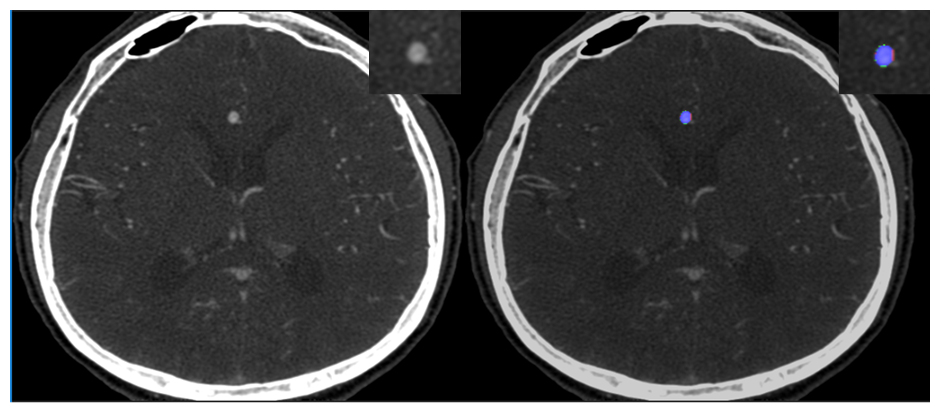

Detects and localizes unruptured cerebral aneurysms using deep learning. Marks aneurysm locations, outlines, and diameter ranges on CTA images.